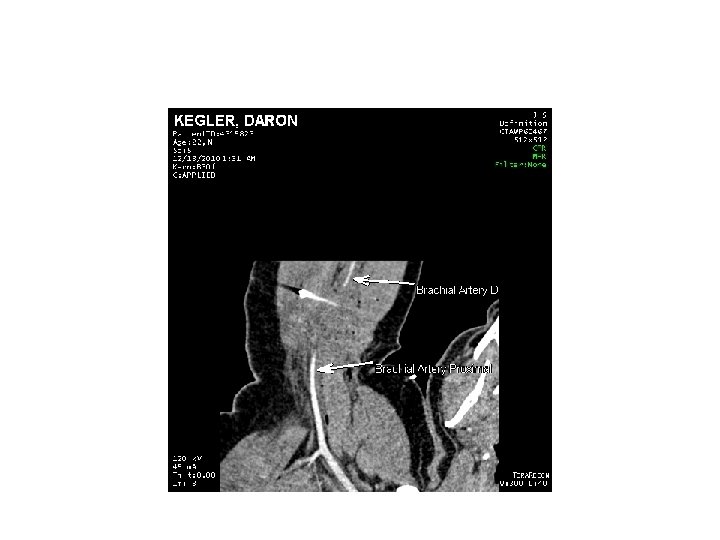

CTA